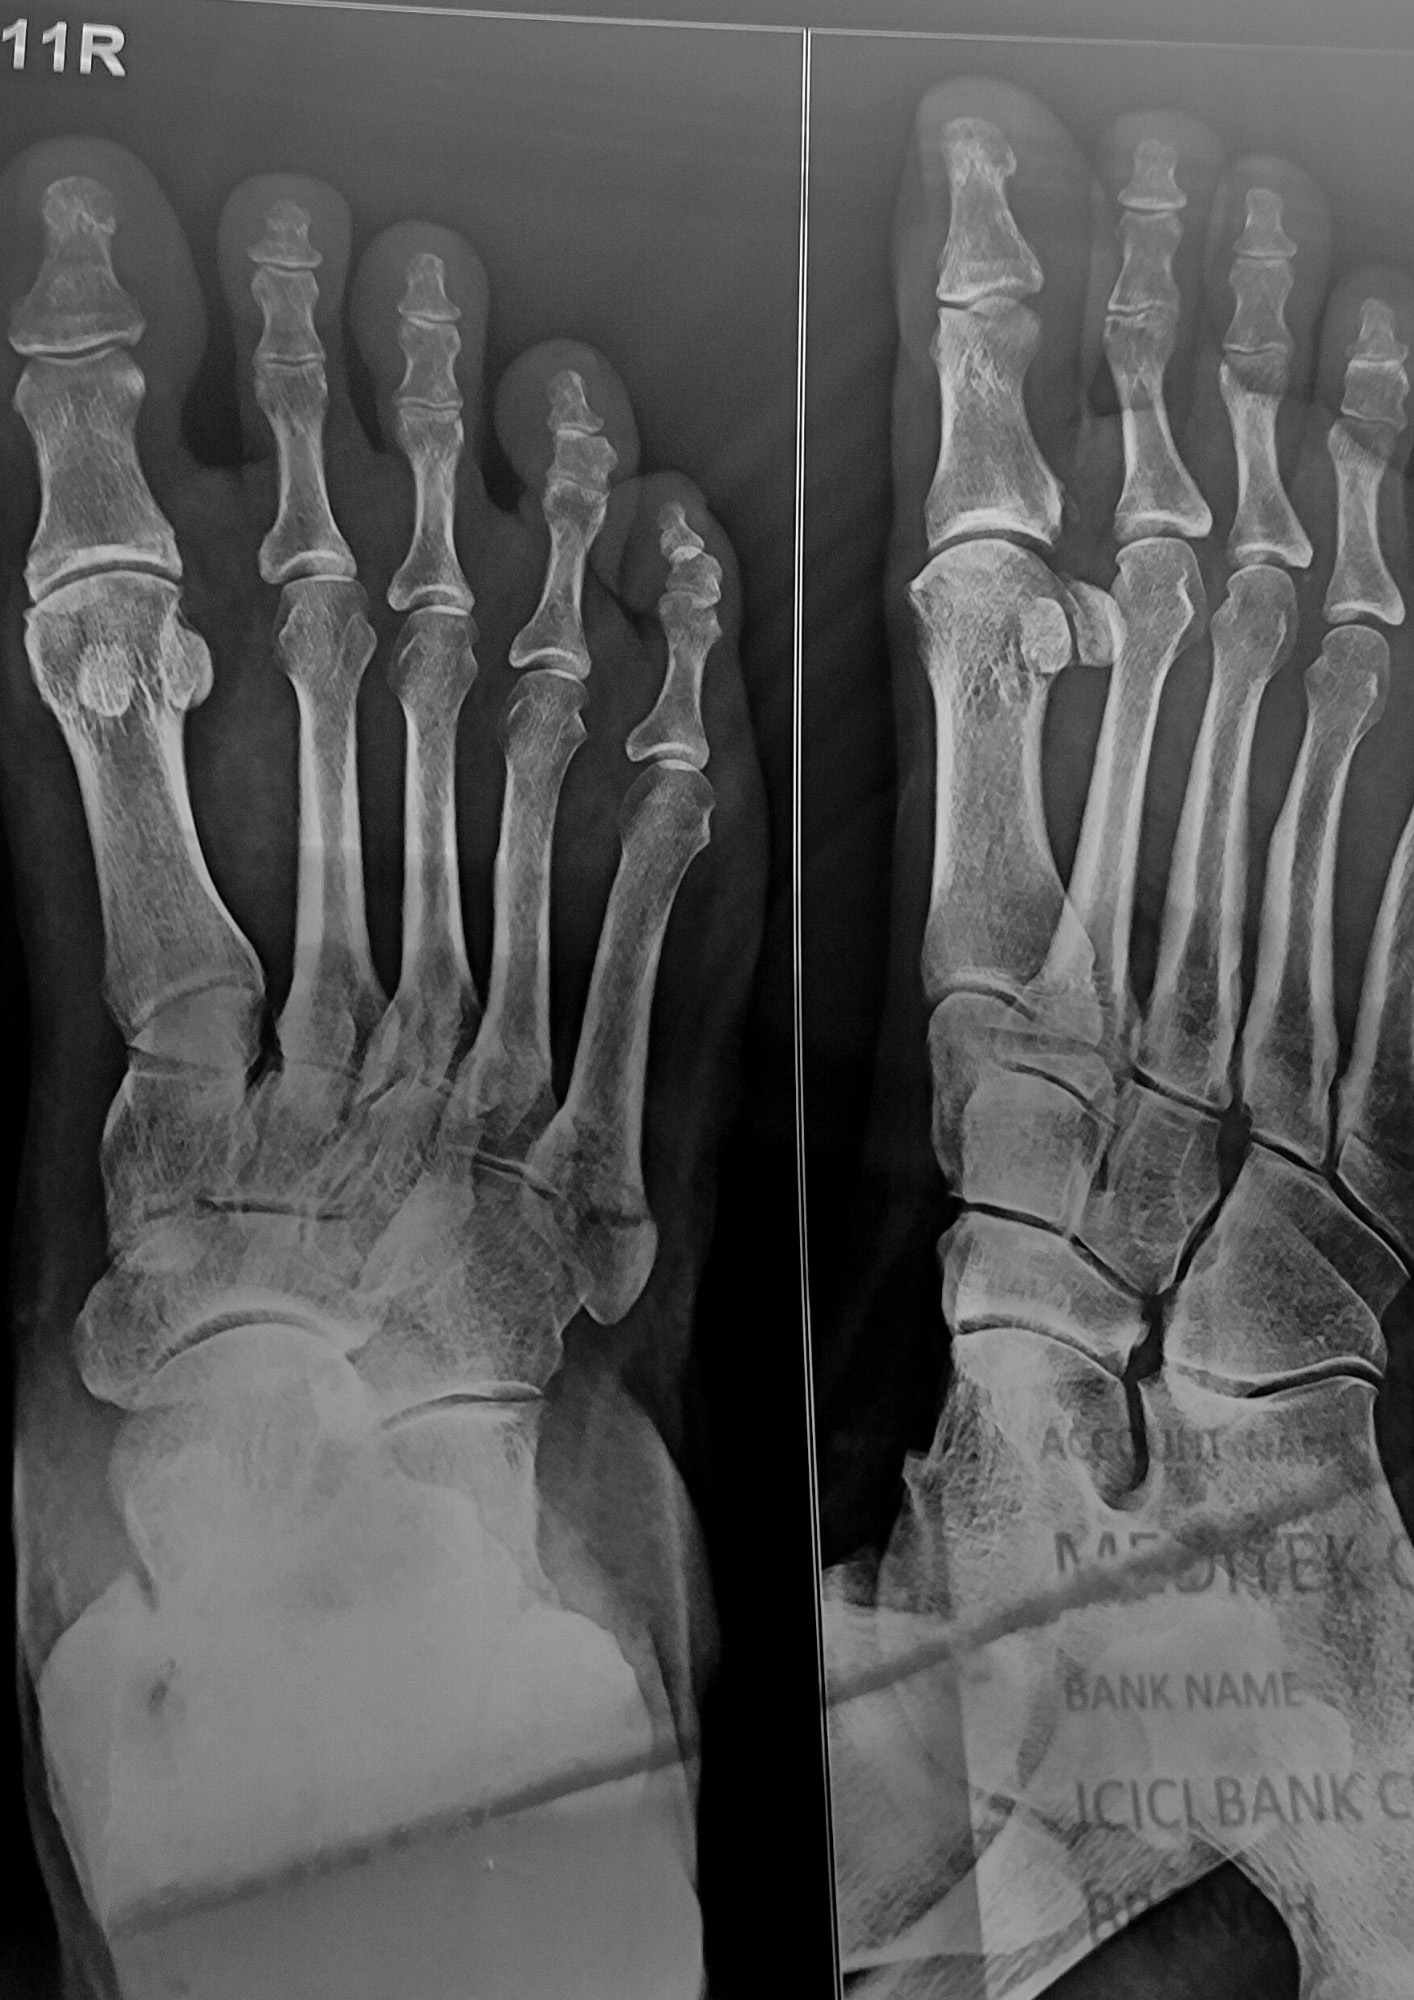

X-ray (2022)

An x-ray of Roychowdhury’s mother’s foot after a fracture. Held up against a light box inside the clinic, a portion of the clinic’s bank details are visible in the lower right corner, highlighting the capitalist “skeleton” of healthcare—a basic human right.